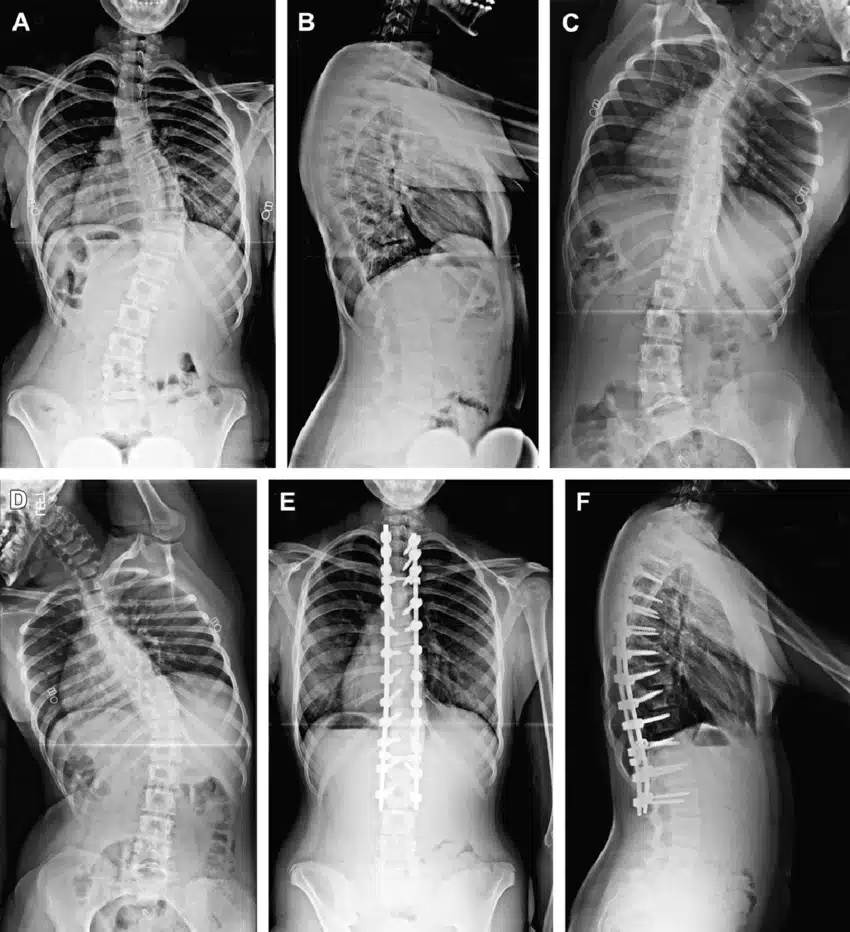

يمكن أن يحدث تضيق القناة لعدة أسباب. وأكثر سببين شيوعاً هما الشيخوخة والتهاب المفاصل. ويعود السبب في حدوث التهاب المفاصل إلى تلف الغضاريف، أو تطعيم العظام أو فرط نمو العظام. مع تقدم الإنسان بالعمر ، يتعرض جسم الإنسان لبعض العمليات التنكسية ، وقد تصبح الأنسجة في العمود الفقري أكثر سمكاً، وتنمو العظام بشكل أكبر من حجمها الطبيعي ، مما يشكل ضغطاً على الأعصاب. ويمكن أن تؤدي الشيخوخة أيضاً إلى حالات أخرى مثل الفُصَالٌ العَظْمِيّ (هشاشة العظام) والتهاب المفاصل الروماتويدي ، وكلاهما حالة التهابية يمكن أن تؤدي إلى تضيق القناة. يمكن أن يؤدي هشاشة العظام إلى حدوث تغييرات في القرص الفقري، وسماكة أربطة العمود الفقري ، وفرط نمو العظام، حيث تسبب هذه الحالات ضغطاً على الحبل الشوكي والأعصاب. ويمكن لأسباب أخرى بالإضافة إلى العمر والتهاب المفاصل ، أن تسبب تضيق القناة ومن هذه الأسباب ( العيوب الخلقية، انحناء العمود الفقري ، الجنف وأورام العظام ) بالإضافة إلى الأسباب المحتملة الأخرى مثل حدوث بعض الإصابات التي قد تسبب كسور أو التهاب في العمود الفقري أو بروز الأقراص الفقرية.

مُعظم الأشخاص المصابين بالتضيُّق الشوكي هم فوق سِنِّ 50. على الرغم من أن التغيُّرات الانتكاسية يمكن أن تسبب تضيُّق العمود الفقري لدى الشباب، إلَّا أَّن هناك أسباباً أخرى يجِب أخذُها في الاعتبار. وتشمل هذه الأسباب: الإصابة، تشوُّهات العمود الفقري الخِلقية مثل الجنف، والأمراض الوراثية التي تؤثر على نموِّ العظام والعضلات في جميع أنحاء الجسم. يمكن أن يُميز التصوير الفقاري هذه الأسباب.